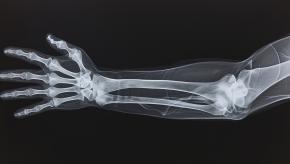

Five Fractures You Don’t Want to Miss

In orthopedic practice, missing the wrong fracture can significantly alter a patient’s outcome. Certain injuries may appear subtle on initial imaging yet carry serious consequences if not promptly recognized and managed. Below are five fractures that warrant a high index of suspicion due to their risk of displacement, nonunion, or long‑term degenerative change.